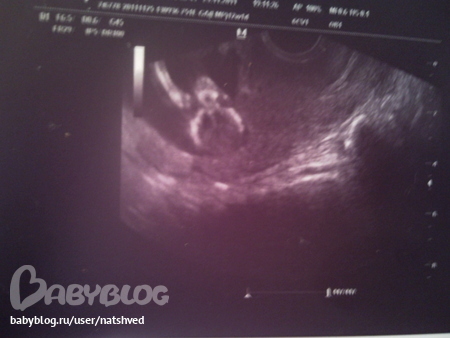

Сегодня же ходила на первый скрининг, так мило!!!! Мой малыш в полном порядке, все соответствует норме, КТР 62мм, БПР 17,3мм, ДБ 7,5мм, ТВП 1,2мм, ЧСС 159 уд./мин.. Нос, ручки, ножки, желудок, сердечко, позвоночник, пальчики и половой отросточек - все есть! Активно шевелемся, переворачиваемся. В начале узи он был спиной кверху, потом перевернулся спиной вниз, потом на бок спиной, потом животом, а в конце вообще вниз голвой))) Сначала все челюстями чмокал, вроде как ел или пил)))Рассмешил меня, когда врач показала, что он двсе время держит одну руку между ног))))начесывает там себе что то, так делают в основном мальчики, мне кажется))))но она по углу отростка предположила, что это скорее всего девочка! Я так и знала! Не зря сны снились. Хотя, думаю, что рано еще для точного определения пола. Так что будем ждать 20 недель. Мужу и сыну сказала, что предположительно девочка, расстроились. А я сказала: ну и хорошо! помощница будет!

А вот и фоточки: на верхнем, как будто улыбается))), на средней инопланетянин, а на нижней рукой махает)))